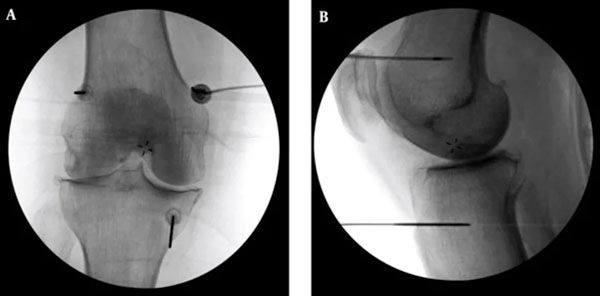

李宜轩解释,中度以前多能藉由药物、复健、肌力训练、生活调整与体重控制改善,至于中晚期则可能需要置换人工关节。针对不适合手术或不愿手术的患者,可采用“高频热凝疗法”止痛,治疗在局部麻醉下进行,医师以X光定位,将电极导针置入膝盖三处感觉神经丛,并输出高频电波,以热能阻断疼痛传导,达到止痛效果。

为确保施行过程中未伤及运动神经,治疗前会先进行电量测试并请病人活动膝盖,确认安全后再施行。多数患者术后当下至一周内即可感受改善,效果约可维持半年~2年不等。若有急性感染、心律调节器或服用抗凝血剂者则不适用,须由医师评估。